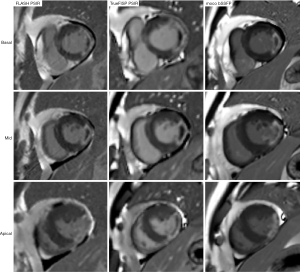

The overall IQ score and contrast-to-noise ratio (CNR) were used to comprehensively evaluate IQ. First, LGE images were randomized and scored for overall IQ using a previously established 4-point-scale based on the American Heart Association (AHA) 17-segmented model (13). The standard was as follows: (I) severe artifact and not analyzable; (II) moderate artifact but can identify the infarct area; (III) mild artifact but no impact on diagnosis; and (IV) good IQ, no artifacts. Only patients with an IQ score ≥2 were included for further LGE image quantitative analysis. Figure 1 shows the LGE image of the score 1–4. Besides, for the score of 1, the reason contributing to the image artifacts was analyzed and recorded. Then, the signal intensities (SIs) of NM, LGE, and MVO were measured. MVO was defined as a hypoenhanced area within hyperenhanced myocardium. The standard deviation (SD) of background noise signal was measured from the region of interest (ROI) located outside the patient, and the ROI was nearly circular in shape with the average diameter of 5 mm. The CNRs were calculated with the following formula: CNR(LGE-NM) = (SILGE − SINM)/SD. In addition, we also evaluated the percentage of signal enhancement (%SE) (14,15), and the formula was as follows: 100%× (SILGE − SINM)/SINM.

The overall IQ scores of the FLASH PSIR, moco bSSFP, and TrueFISP PSIR for all patients were 3.45 (3.07, 3.64), 3.89 (3.8, 3.91), and 3.91 (3.82, 4), respectively. The overall IQ score for moco bSSFP and TrueFISP PSIR was significantly higher than turbo FLASH (P<0.001). The overall IQ score of moco bSSFP was significantly higher than that of TrueFISP PSIR (P<0.001). The LGE image of a typical patient is illustrated in Figure 3. To further investigate the differences in overall IQ scores of the three LGE sequences between the three groups, we performed a subgroup analysis. The same results were finally obtained, as detailed in Figure 4.